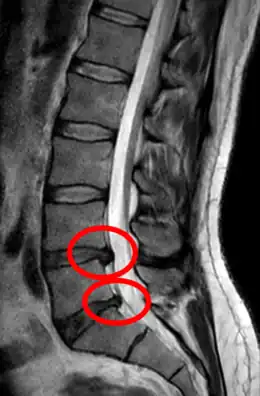

L'imagerie par résonance magnétique peut montrer la hernie, le canal vertébral, les nerfs, les tissus environnants. Les tissus mous sont les mieux analysés par cet examen qui est le plus performant pour le diagnostic de hernie discale. Les images pondérées en T2 montrent clairement la hernie.

IRM lombosacrée sagittale montrant une hernie discale de niveau L4-L5.